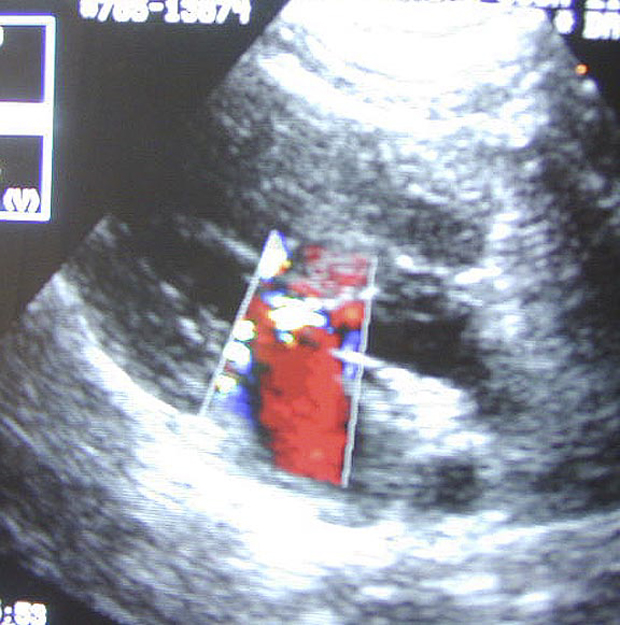

PDA Echo Findings YouTube Pda Dog Heart Patent ductus arteriosus (also called pda) is a birth defect in the heart. Patent ductus arteriosus (pda) is one of the most common congenital heart defects in dogs. What is patent ductus arteriosus? Recognition of findings and clinical signs as well as the echocardiographic findings can help the clinician to act quickly, allowing the best outcome for patients with pda.. Pda Dog Heart.

Echocardiogram of PDA in a Dog YouTube Pda Dog Heart Patent ductus arteriosus (pda) is one of the most common congenital heart defects in dogs. Patent ductus arteriosus (also called pda) is a birth defect in the heart. Failure to identify and close a pda can result in premature death,. Patent ductus arteriosus (pda) is a common form of congenital heart disease in dogs (schrope, 2015; Recognition of findings and. Pda Dog Heart.

Canine patent ductus arteriosus (PDA) echocardiography Vet Practice Pda Dog Heart It is caused by incomplete changes in the heart's circulation when a dog or. A pda occurs when the ductus arteriosus (which. Patent ductus arteriosus (pda) is a common form of congenital heart disease in dogs (schrope, 2015; Failure to identify and close a pda can result in premature death,. What is patent ductus arteriosus? Recognition of findings and clinical. Pda Dog Heart.